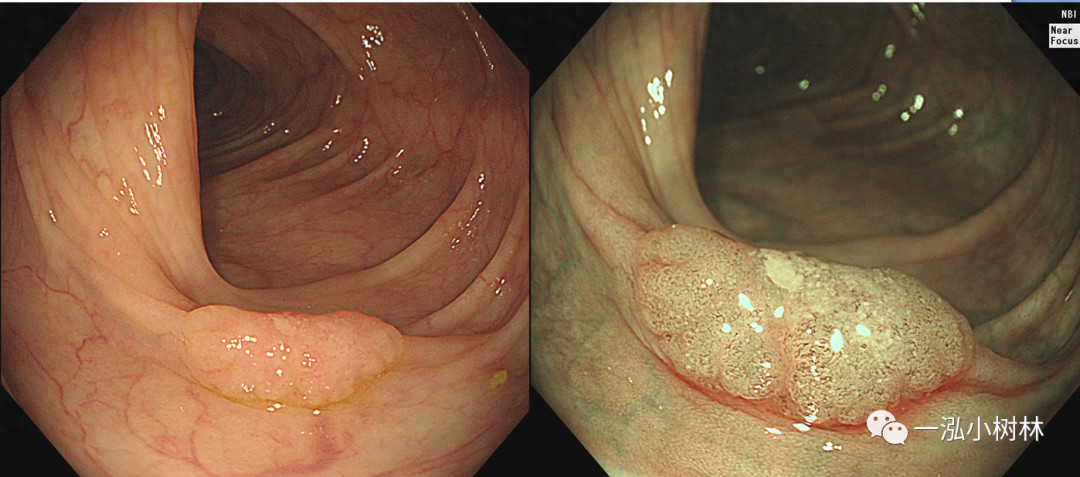

图4 结肠管状腺瘤(Pit Pattern IIIS+IIIL型)